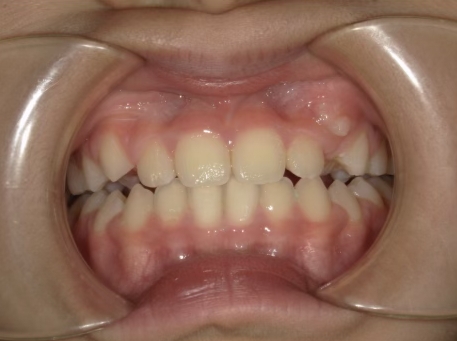

治療中⑤ 小5:10y11m

モノブロック装置継続中、左上3が八重歯で萌出